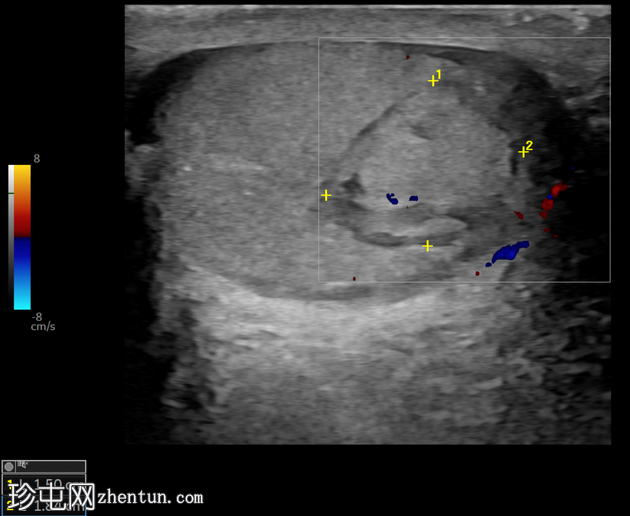

左侧睾丸超声显示一个边界清晰、无血管的周边等回声病灶,周围有低回声环,白膜完整,并伴有阴囊壁增厚。

睾丸内血肿通常由睾丸外伤引起,在急诊超声检查中表现为圆形等回声或高回声无血管区,通常位于睾丸周边。白膜完整可将其与睾丸破裂区分开来。

急性钝性睾丸外伤史伴压痛对于诊断至关重要,有助于排除睾丸

肿瘤

和节段性睾丸梗死等其他疾病。建议进行随访超声检查以确认病灶是否消退。